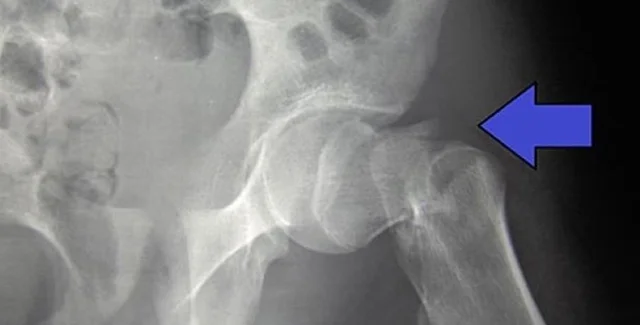

Только на переломы бедра приходится 1,8 миллиона койко-дней и 1,1 миллиарда фунтов стерлингов на больничные расходы каждый год, не считая высокой стоимости социальной помощи. Цель исследования состояла в том, чтобы выяснить, могут ли механические вибрации улучшить то, как наши тела обрабатывают и реагируют на небольшие колебания тела.